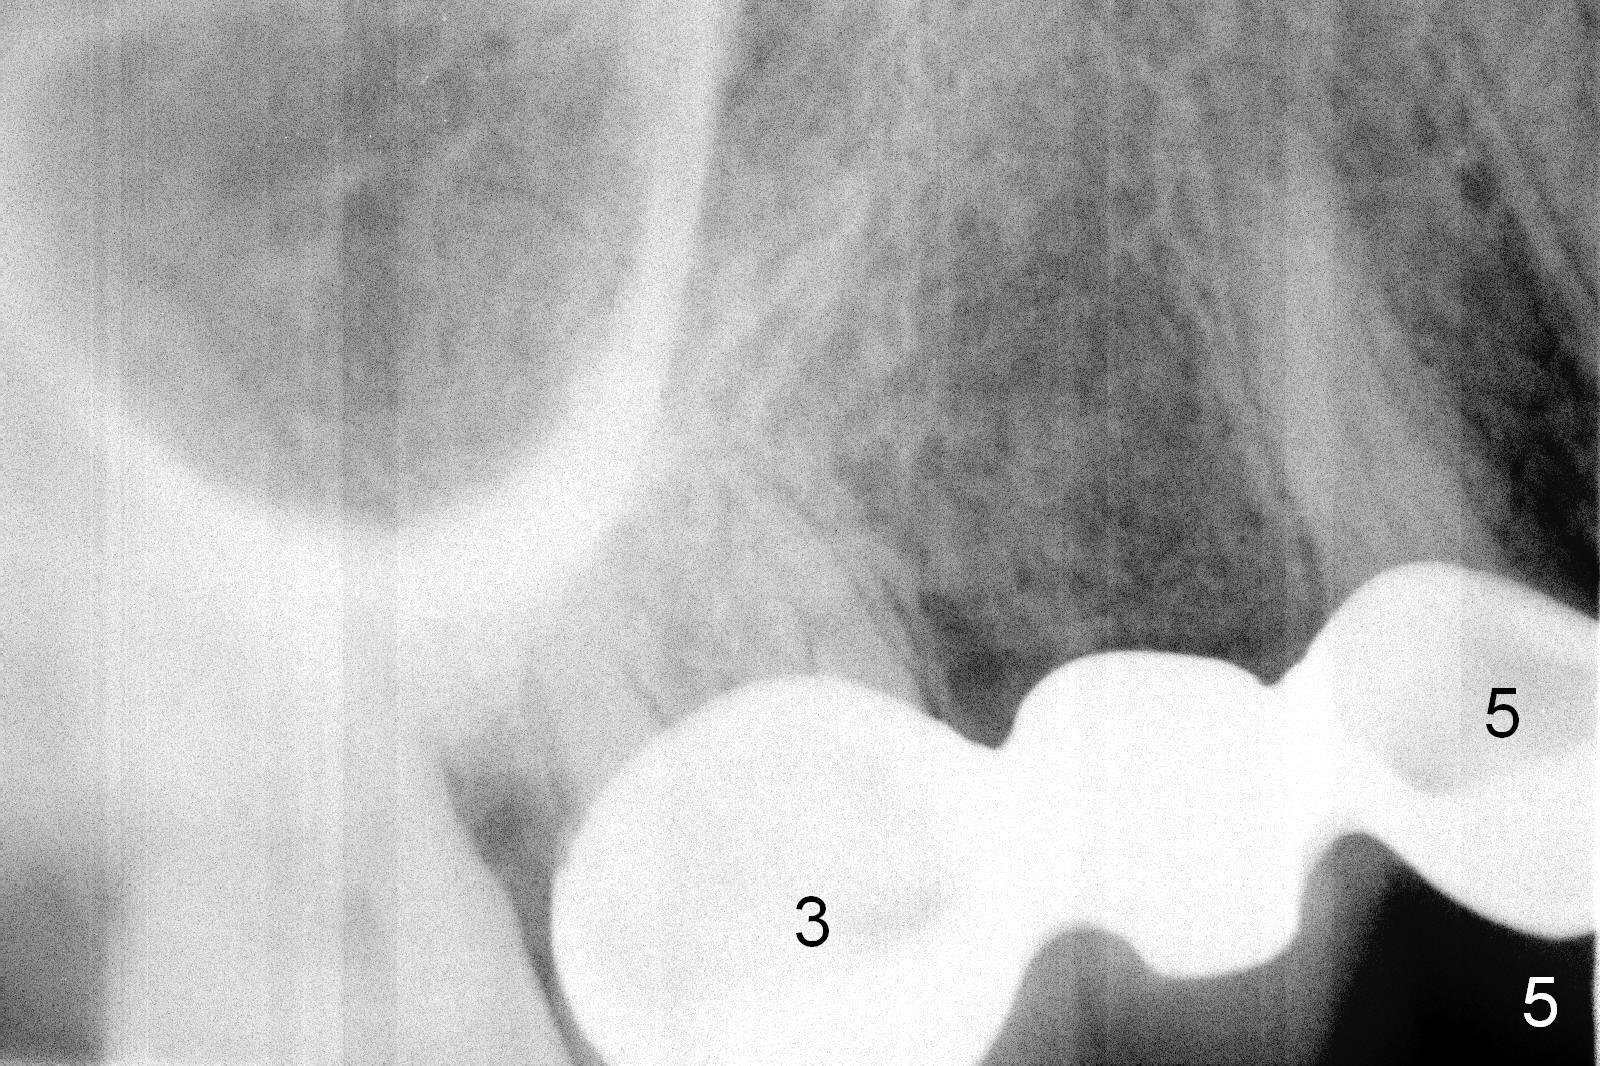

Ms. Li, a 34-year-old lady, had the upper right fixed partial denture made by an unlicensed dentist in California 10 years ago (Fig.1: #3-5). The gingival margin palatal to the retainers is erythematous (Fig.1 arrows). The patient's chief complaint is gum bleeding. The retainer at #3 is over-contoured buccopalatally (Fig.1, as compared to #14 in Fig.2), while the one at #5 is over-contoured buccopalatally and mesiodistally (compare to #12 in Fig.2). Panoramic X-ray (Fig.3), bitewing (Fig.4) and periapical film (Fig.5) all confirm that the bridge is over-contoured and that the retainers #3 and 5 have open margin (Fig.4 arrowheads). To improve oral hygiene and save the abutment teeth #3 and 5, it is in the patient's best interest to remove the bridge, place an implant at #4 and fabricate single-unit crowns at #3 and 5. Three to four months later, pyogenic granuloma develops between #4 and 5 (Fig.6 *) with generalized gingival erythema apically. The pontic at #4 and the retainer at #5 are to be removed first. An implant will be placed at #4 (Fig.7) with conjoined provisional at #4 and 5. The initial depth of osteotomy is 13 mm with Sinus Master Kit.